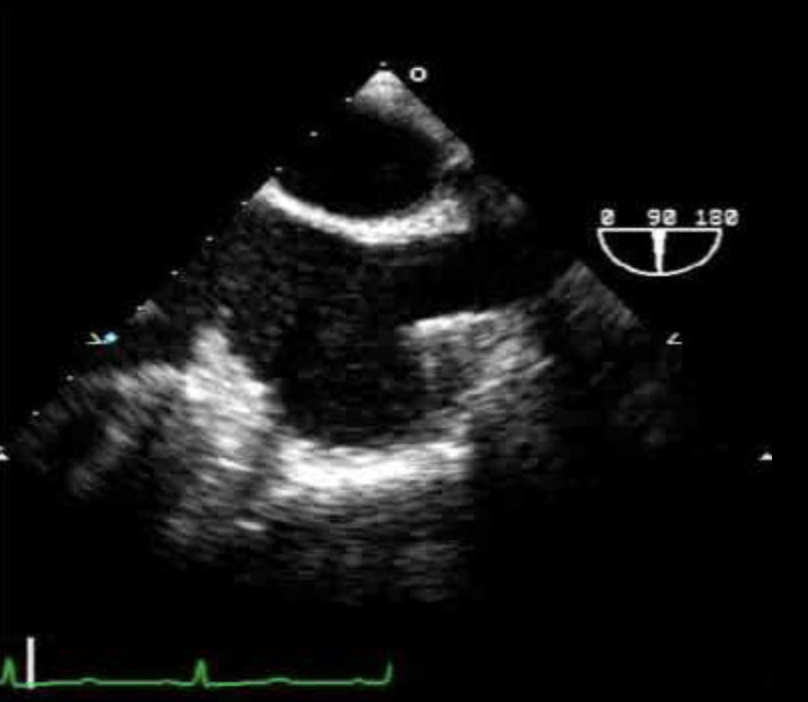

Mid-Esophageal 4-Chamber (ME 4C)

- ME

- Winkel 0°

- Zielstrukturen

- Bisschen wie A4C

- Ziel: TK Durchmesser maximieren

- Ziel: AK/LVOT nicht sichtbar (→tiefer)

- Danach ME 2C